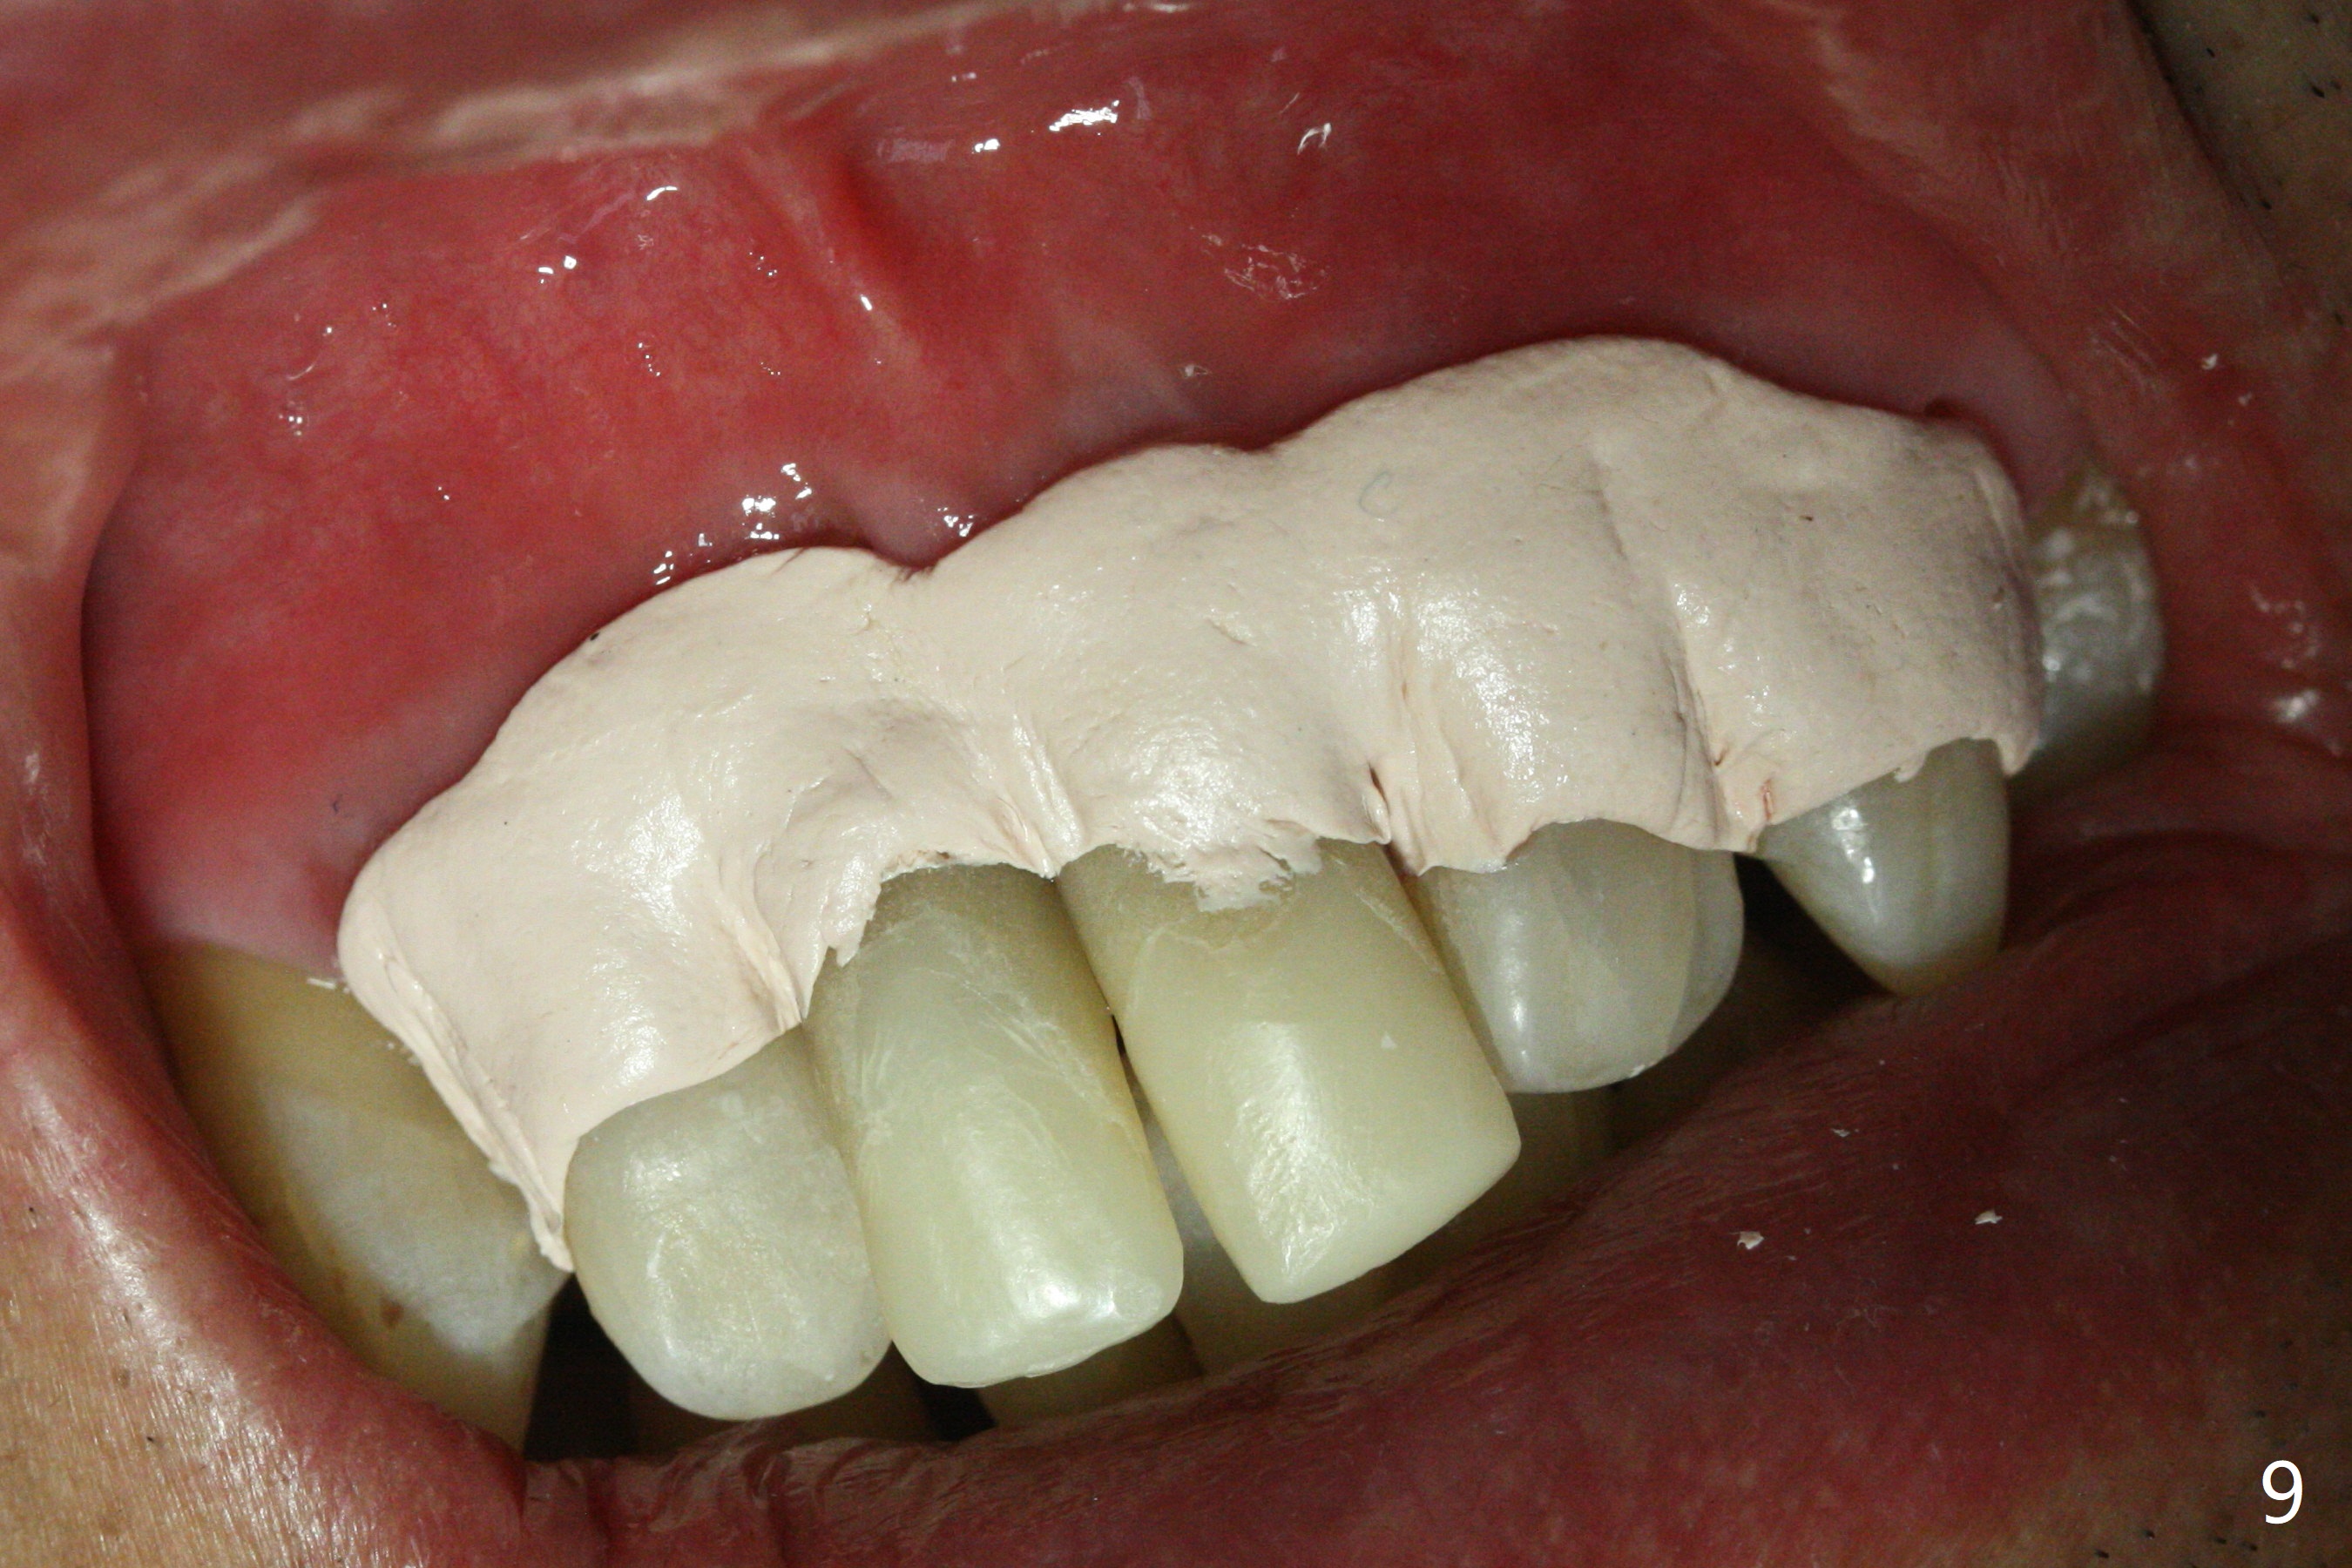

The gingiva remains recessive at #8 and 9 six months post immediate implant placement with bone graft (Fig.1). The buccal plate at #8 is particularly concave before (Fig.2 *) and after (Fig.3) abutment removal. The bony defect repair is assisted by placing a 4 mm tenting screw between the 2 implants (Fig.4) and placing allograft mixed with PRF (as putty) around the screw (Fig.5 (after replacement of the abutments)). The buccal contour improves because of the tenting screw and the bone graft placement (Fig.6 (as well as PRF and 6-month membranes)). The wound dehisces 12 days postop and immediately before leaving country for months (Fig.7). The sutures are removed, Osteogen plug is inserted (Fig.8) and periodontal dressing is applied (Fig.9). PA is taken to show the tenting screw (Fig.10 T). The latter is exposed 3 months postop (Fig.11,12). It appears that gingival graft is a must (Fig.13). Make a palatal stent, remove the temp with abutments and create a bleeding surface before harvesting a large piece of tissue. Connective tissue graft is done 5 months post bone graft (Fig.14). In fact there is no implant thread exposure. In fact the connective tissue graft does not survive. The abutments are re-prepared for pink porcelain (Fig.15). The bone loss is stable 1 year post cementation in spite of incomplete abutment seating (Fig.16). The soft tissue is nearly normal (Fig.17).